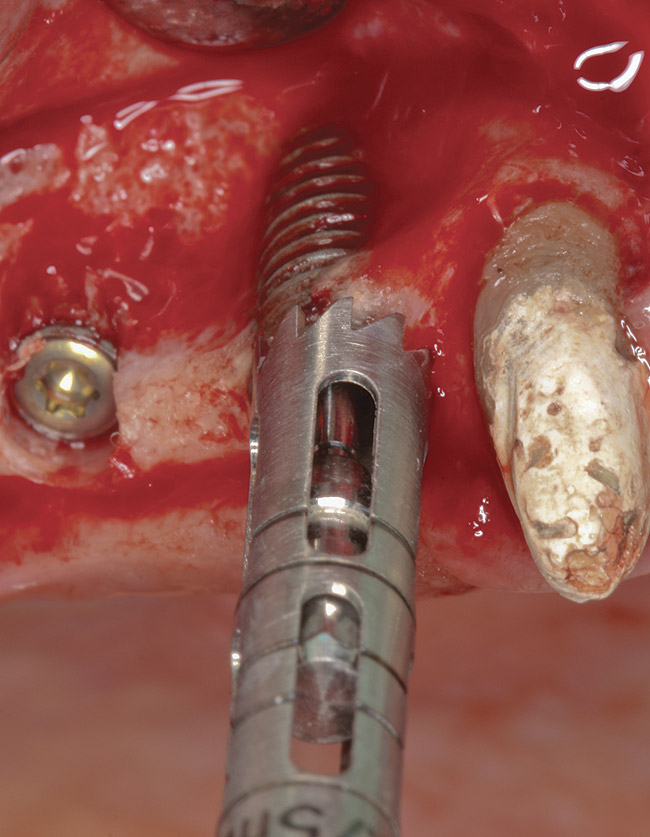

Figure 3  The implant was explanted by using a counter-torque ratchet.

Figure 3

Figure 12  Trephine bur used to remove bone around the failed implant guided by the implant mount.

Figure 12

Figure 13  Combination technique with the counter-torque ratchet used following bone removal with the trephine bur.

Figure 13